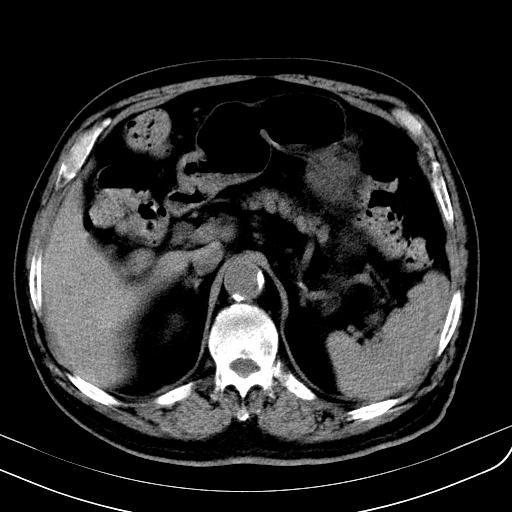

胃底靠近胃大弯处可见一圆形软组织影,直径为3.45cm,ct值约为30.1hu

胃底间质瘤

考虑为胃底间质瘤

胃底良性肿瘤,考虑间质瘤

边缘光滑,密度均匀,良性占位,首先考虑平滑肌瘤。

边缘光滑,密度均匀,良性占位,首先考虑平滑肌瘤。其实平滑肌瘤也是间质瘤的一种